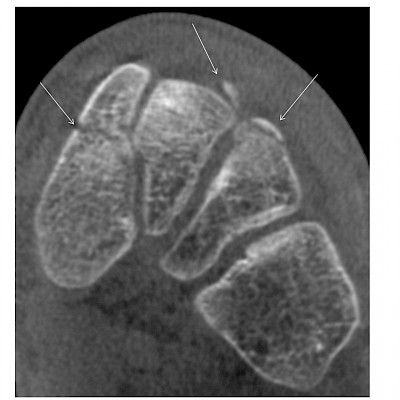

Magneettikuvaus valtaa alaa eturauhassyövän diagnostiikassa Eturauhassyöpää epäiltäessä otetaan tavallisesti peräsuolen kautta kaikukuvausohjauksessa 10–12 neulanäytettä eturauhasesta. Toimenpiteen ongelmia ovat suuren riskin potilaiden alidiagnostiikka ja kliinisesti merkityksettömien syöpätyyppien ylidiagnostiikka. Eturauhasen magneettikuvaus on havaittu käyttökelpoiseksi kynnystutkimukseksi, jonka avulla voidaan välttää biopsia, jos tulos on negatiivinen. Positiivinen tulos puolestaan mahdollistaa näytteenoton kohdennetusti. Ossi Lindell Lehti 22: Lääketieteen maailmasta 22/2018 Kommentteja